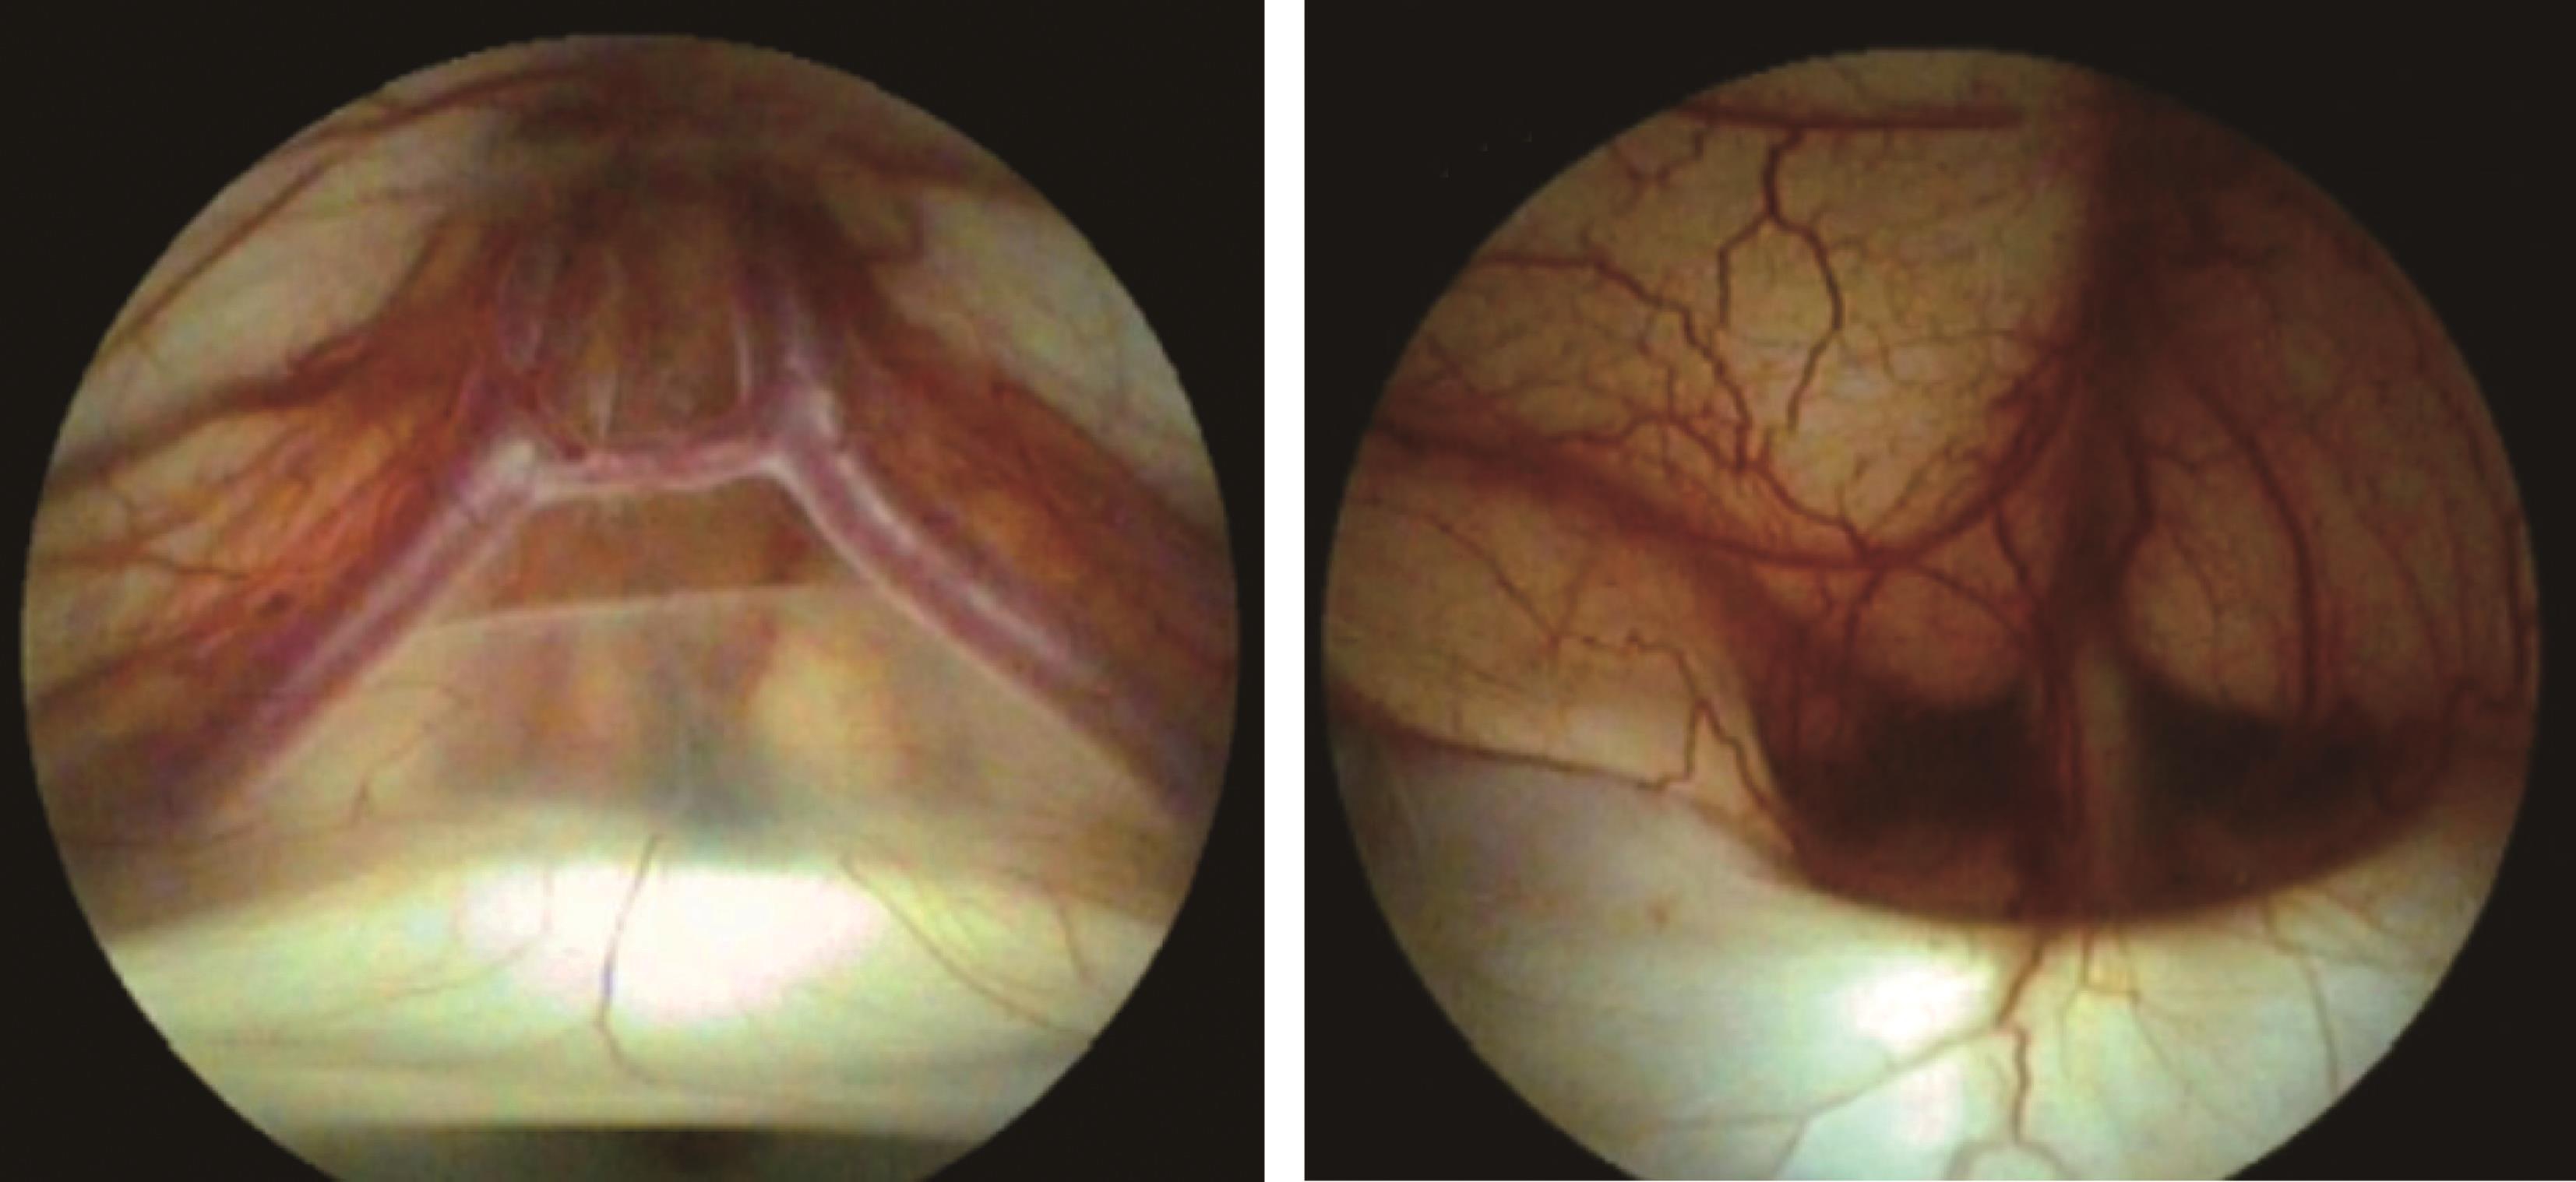

图3-1-1-1 出血后脑积水的脑室演变

a.发病时头颅CT:脑室内血肿呈高密度;b.发病12天后复查CT:血肿已呈低密度;c.发病5个月后头颅MRI:脑室明显扩张,脑室内未见异常信号;d.内镜下探查见脑室内仍有陈旧血斑及含铁血黄素沉积